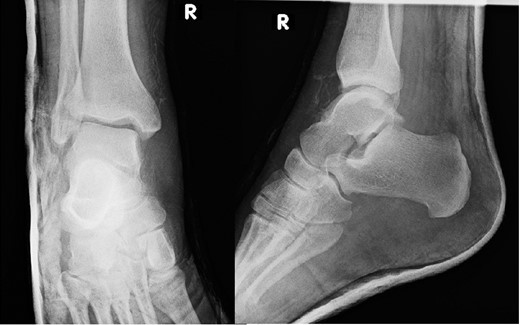

A 30-year-old male patient presented to Emergency Department (ED) following a run over injury. The patient described the mechanism of injury as moving his body over his run over foot. On clinical examination, there was obvious deformity and swelling of the right ankle. Dorsalis pedis pulse was felt but weak compared to the contralateral side with a capillary refill time under 3 s. The posterior tibial artery could not be palpated because of the deformity. X-rays showed posterior ankle dislocation without associated fractures (Fig. 1). Urgent reduction of the dislocation was done under sedation in ED. The knee was first flexed to relax the tendon Achilles then longitudinal traction with gentle forward force applied to the heel with immediate reduction of the deformity achieved. The foot was reassessed for vascular status. Triphasic pulse in both drosalis pedis and posterior tibial artery was detected with hand held Doppler. Ankle was immobilized in posterior below knee back slab to accommodate for swelling and check x-rays confirmed reduction of the ankle joint (Fig. 2). CT scan was done afterwards to define any subtle incongruity or osteochondral fragments entrapped in the joint. CT did not show any associated fractures and showed congruent reduction of the ankle joint (Fig. 3). Patient was mobilized touch weight bearing for first 2 weeks. The back slab was changed for weight bearing short leg cast and progressive weight bearing was allowed for the following 4 weeks. At 6 weeks follow up, plaster was removed and on examination patient still had moderate tenderness over the medial joint line and deltoid ligament area. Also, patient had limited range of plantar and dorsal flexion. Referral for physiotherapy was done for start of functional rehabilitation and range of motion exercises and in mean time MRI was done to delineate extent of ligamentous injury. MRI showed bone bruising of the lateral malleolus, medial malleolus and lateral talus (Fig. 4). The anterior talufibular ligament (ATFL), calcaneofibular ligament (CFL), posterior talofibular ligament (PTFL) and deltoid ligaments were sprained but intact. At 12 weeks follow up, patient could walk normally without any symptoms of instability and achieved 20° of both plantar and dorsal flexion. At 16 weeks, patient achieved full range of motion of ankle and was able to return to work. At 24 weeks follow up patient was able to resume his sport activates as preinjury level.

Plain film X-rays of right ankle showing total posterior dislocation of the ankle joint with no fracture of the medial or lateral malleolus.